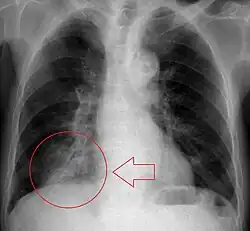

Radiologic studies may be done to image the chest wall, lungs, and airway to evaluate and diagnose conditions that may be contributing to aspiration, and also to diagnose complications of previous aspiration.

Chest X-rays can be useful in the diagnosis of aspiration pneumonia but may be negative early in the course.[12] Chest CT Scan can identify the presence of a pneumonia as well, and can also assist in characterizing abscesses, foreign objects, or pleural disease.